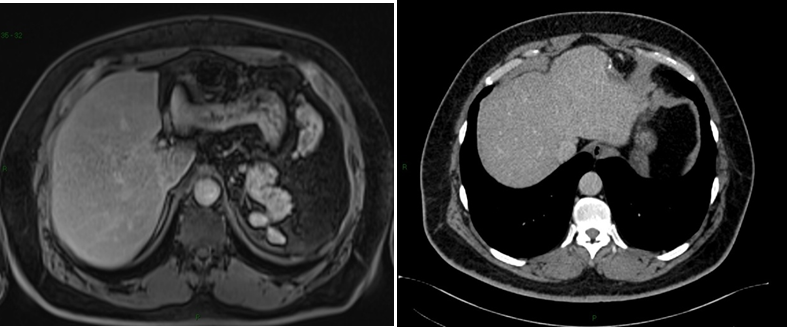

Intrahepatic splenosis shows increased enhancement on CT or MR images during the arterial phase. Performing gadoxetic acid–enhanced hepatocyte-phase MR imaging does not help because intrahepatic splenosis is hypointense during the hepatospecific phase. The MR technique involving administration of small iron oxide particles (SPIO-Endorem), which is taken up by liver and spleen reticuloendothelial cells, has proven to be effective in differentiating intra-hepatic splenosis from other lesions.14,15,18 With SPIO (superparamagnetic iron oxide) intrahepatic splenic nodes remain hyperintense.19 Noncontrast CT reveals a well circumscribed iso- or hypodense mass in the liver, while noncontrast MRI demonstrates mild-to-moderate hyperintensity on T2-weighted image and hypointensity on the T1-weighted image. A dynamic study on CT and MRI shows a slight to intense enhancement, which may be homogeneous or heterogeneous during the arterial phase but enhancement is diversely during the portal venous and equilibrium phases in different cases. Compared with the surrounding hepatic parenchyma, the lesion could reveal hypodensity and hypointensity, or hyperdensity in the arterial phase. Or it can demonstrate diminished enhancement, slight enhancement, or increased enhancement during the following phases (Figure 2 & 3).19,20

Figure 3Postoperative figures A, B, C, D and E. Computed Tomography (CT). Postoperative CT in the axial plane in the post-contrast venous phase show signs of partial resection of the liver segment II (A,B, C and D), as well as splenectomy with small implants of splenic tissue in the left subphrenic region (E).

In standard imaging techniques, such as US, CT-scan, or MRI, the hepatic splenosis may mimic adenoma, hepatocellular carcinoma, or metastatic liver neoplasms.8,21 In the imaging studies, the diagnosis was not definitive and hence the need for an invasive procedure.

The keys to diagnose intrahepatic splenosis are knowledge of splenic injury, the subcapsular location of the lesion (mostly in the left liver lobe), and the association with other hypervascular intraperitoneal lesions.22 If intrahepatic splenosis is suspected, technetium-99m–labeled red blood cell scintigraphy should be performed and represents the most specific imaging technique.8,22,23 Histology represents the gold standard for the diagnosis.8,24 Sometimes, laparoscopy is necessary for biopsy. Histologically, liver splenosis presents as nodular lesions rich in lymphoid tissue and hematopoietic cells, no hilus and its blood supply is derived from surrounding tissues and vessels (Figure 3).5,12 Due to the lack of adequate reported cases, there's no consensus on a gold standard diagnostic approach to hepatic splenosis.14